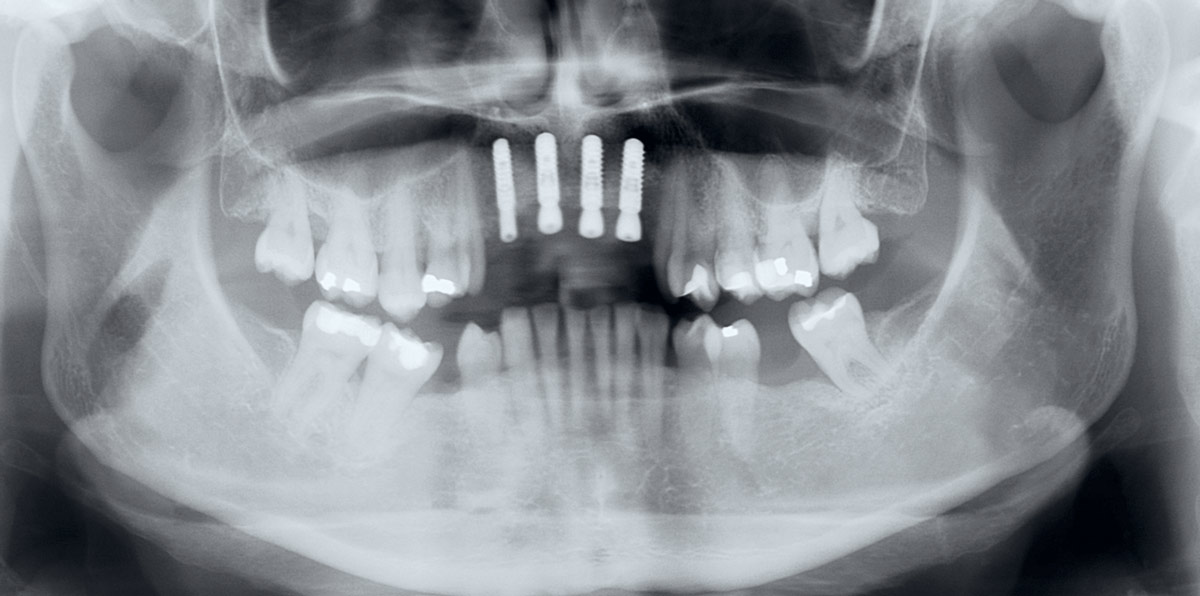

2/17 - Pre-operative x-ray scan: severe bone loss around three failing implantsRestoration of all four incisors with maxgraft® bonebuilder - Dr. Dr. Dr. O. Blume

13/17 - X-ray scan after implant insertionRestoration of all four incisors with maxgraft® bonebuilder - Dr. Dr. Dr. O. Blume

16/17 - X-ray scan after uncovering the implantsRestoration of all four incisors with maxgraft® bonebuilder - Dr. Dr. Dr. O. Blume